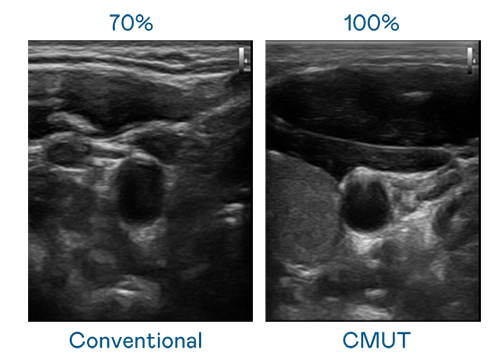

CMUT 技术是一种用电容式微机电元件来产生超音波讯号的技术。与传统 PZT 压电式技术相比,CMUT 频宽增加 30%,更宽频的超音波讯号让影像解析度大幅提升,是实现高影像品质医疗超音波扫描、促进精准医疗发展的关键技术。

超音波影像的解析度高低,首先取决于探头能发出的讯号频宽。九游会ag登录j9入口 CMUT 可提供高清晰的超音波讯号,提供高频宽、高灵敏度、影像纹理细节更高的超音波影像,协助医护人员缩短影像判读时间及利用精准的医疗影像进行诊断。